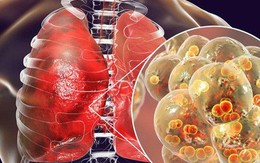

Trời lạnh rất dễ viêm phổi: 8 dấu hiệu "tố cáo" bệnh sớm biết để ngừa biến chứng nguy hiểm

13/12/2018 09:27

Thời tiết chuyển lạnh khiến trẻ em, người lớn tuổi và người có hệ miễn dịch yếu dễ bị viêm phổi. Mọi người hãy cảnh giác với căn bệnh dễ gây biến chứng nguy hiểm này.